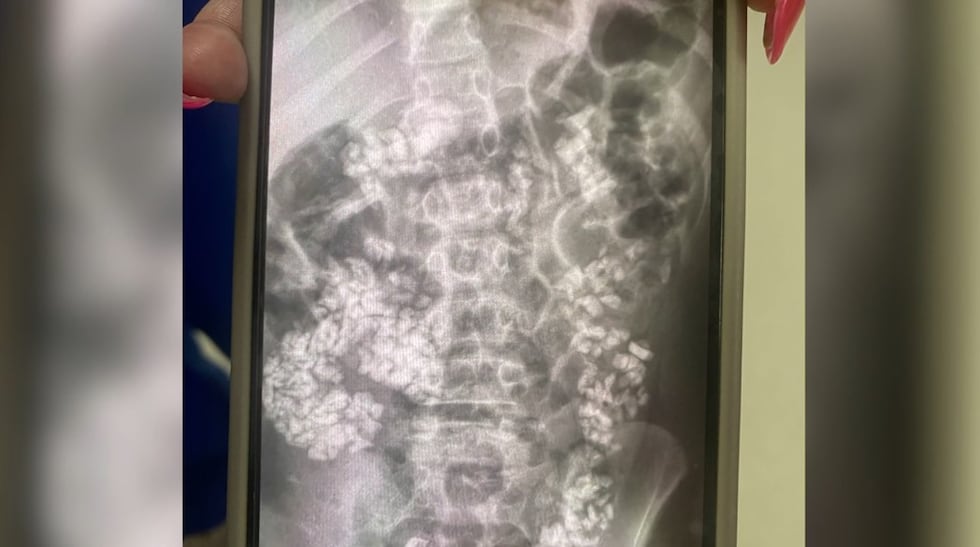

“We were not expecting what we saw when we got the X-ray at all,” she said.

When Whitlow was shown her son’s abdominal X-ray, she says she saw large amounts of gravel throughout his intestinal tract, terrifying her. While the 9-year-old was able to go home that night, she originally wasn’t sure that would be the case. Doctors spoke to Whitlow about possibly taking her son to Cardinal Glennon Children’s Hospital in St. Louis.